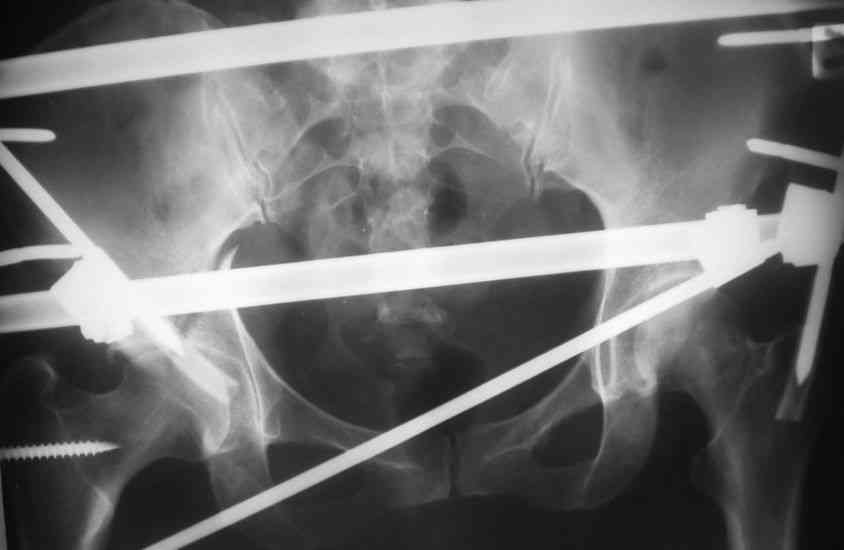

Пациентка 38 лет. В результате ДТП 02.09.06 получила поперечный перелом правой вертлужной впадины, центральный вывих правого бедра, разрыв правого крестцово-подвздошного сустава.

В одной из районных больниц вывих устранен, наложена система вытяжения по оси бедра и за вертельную область. Спустя 2 недели выполнен ВЧКО модулем "таз-бедро". Учитывая возраст пациентки и остаточный диастаз в области свода вертлужной впадины предполагается демонтаж аппарата, открытая репозиция и внутренний МОС вертлужной впадины через внутритазовый доступ.